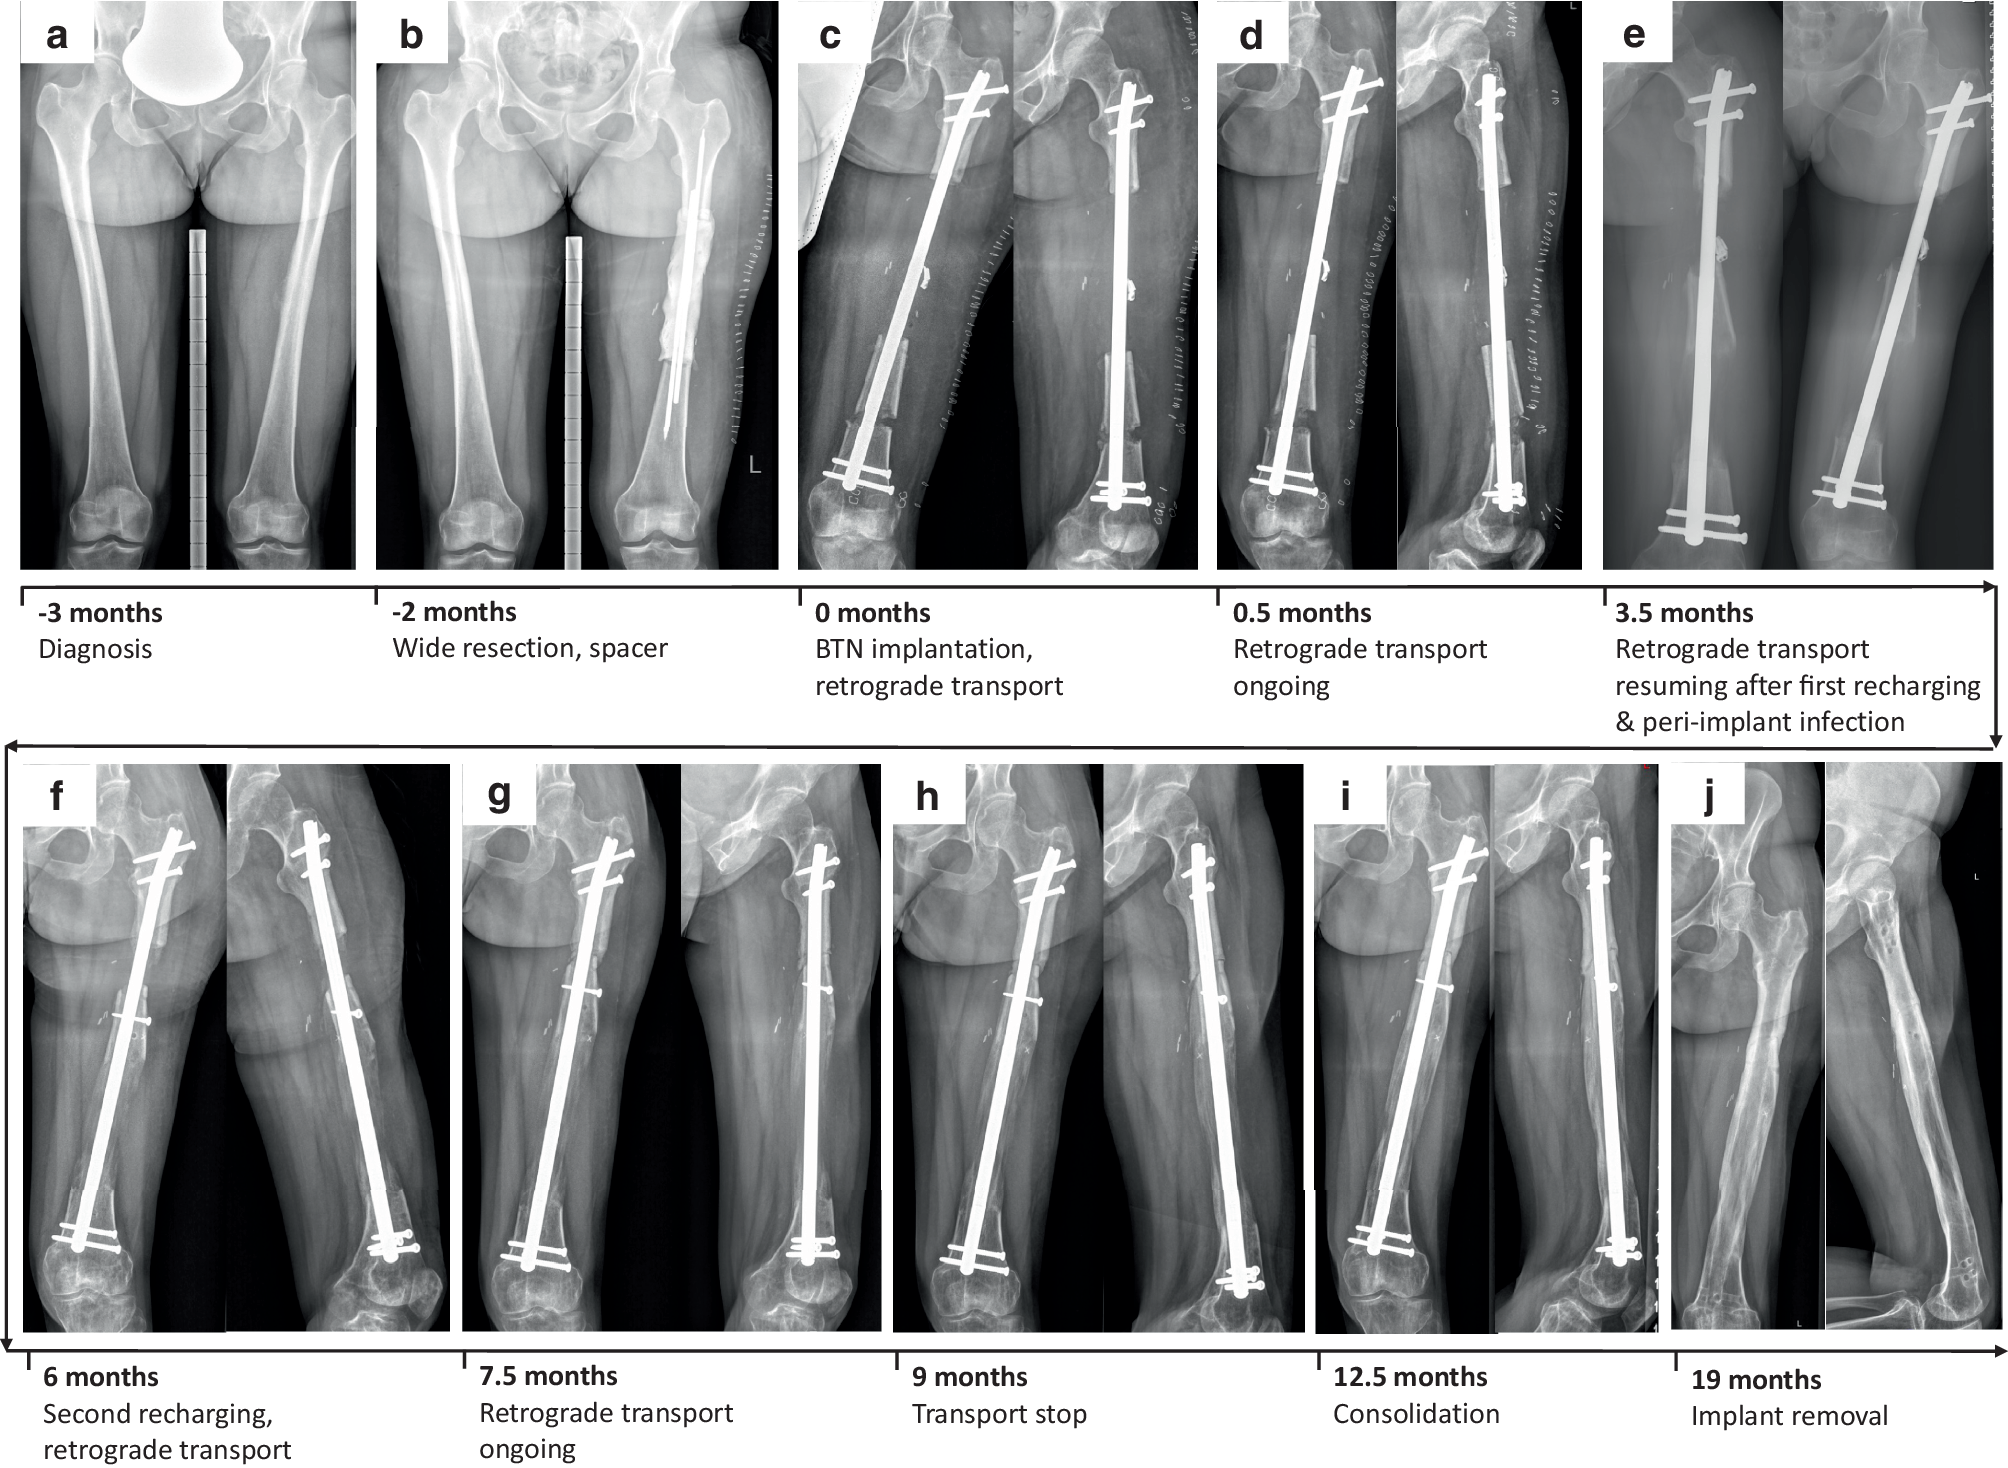

Following histological verification of a periosteal osteosarcoma G2 of the left femoral shaft via open biopsy, a 30-year-old female patient underwent surgical resection of the femoral diaphysis (14.4 cm) and temporary implantation of a cement spacer (Fig. 2a, b). After clear margins had been confirmed, reconstructive surgery with distal femoral osteotomy and implantation of a BTN 11.5/360 mm for retrograde transport were performed (Fig. 2c). The patient was allowed 40 kg partial weight bearing until docking (Fig. 2d). Recharging of the BTN was carried out 2.8 months after implantation. The patient developed a peri-implant infection 3 weeks later, necessitating revision surgery with debridement, lavage and antibiotic treatment (initially i.v., later p.o.; Fig. 2e). After the infection had resolved, another recharging was carried out 2 months later (Fig. 2f). At that time point, the patient was allowed partial weight bearing with half body weight. Bone segment transport was completed 9.1 months after BTN implantation and bony consolidation was achieved soon thereafter (Fig. 2g–i), which was confirmed by CT scan. Surgery to exchange the BTN for a conventional femoral nail was carried out 19 months following surgery. Sonication of the explanted nail to rule out the presence of a low-grade implant-associated infection was inconspicuous. Despite a valgus deformity secondary to bone transport of the femur, the patient was free of complaints, fully weight bearing, with no signs of tumor recurrence or infection (Fig. 2j).

Fig. 2

Clinical course of patient 2 (30-year-old female patient with low-grade periosteal osteosarcoma of left femoral diaphysis. X-ray images of both femurs of patient 2 in anterior-posterior (a.p.) plane taken preoperatively (a) and after resection and spacer implantation (b). X-ray images in a.p. and lateral planes directly following bone transport nail (BTN) implantation (c), at 0.5 months (d) 3.5 months (e), 6 months (f) and 7.5 months (g) with bone transport ongoing, at 9 months when bone transport stopped (h), at 12.5 months when bony consolidation had taken place (i), and at latest follow-up 19 months after BTN implantation, when implant removal had taken place and complete bony consolidation was visible (j)